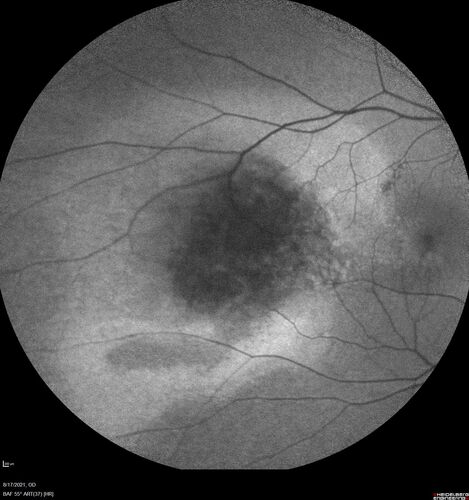

Choroidal Hemangioma Requiring PDT repeatedly

64 year old man.  Diagnosed with hemangioma in 2015.  PDT in 2016.  Images are from 2020 when fluid started to reaccumulate.  Needed PDT repeated two more times.

PDT treatments: [1] 2/19/2015 -  Pavan (IOP  problem after PDT)  AND [2] 11/2/21 PDT (7 mm temporal to fovea) - SMC  AND [3] 7/22/22 PDT 7.5 mm Temporal to the fovea